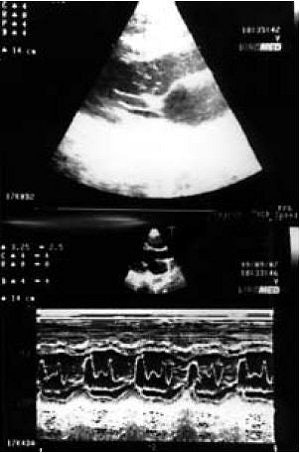

![]() |

| Diastolic 2D frames showing the elongated anterior mitral chordae tendineae in a 15-year-old boy referred for a routine medical examination. He was a member of a basketball team participating in a local championship. No other structural abnormalities of the mitral valve or signs of obstructive cardiomyopathy were noted. |

| Same patient as above. Systolic 2D frame showing the elongated mitral chordae tendineae prolapsing to the left ventricular outflow tracts (arrows) and M-mode recording (lower photo) showing systolic anterior motion and vibration of the chordae. Although the patient was a competitive athlete, he was only advised for follow-up since there was no resting gradient and the elevation of the left ventricular outflow velocity was mild (< 20 mmHg). Several months later, the boy had the same echocardiographic profile but was in excellent health. Vavouranakis I, Lambrogiannakis E, Meidanis K, Nikolaides G, "Prolapse of abnormal mitral chordae tendineae to the left ventricular outflow tract in normal subject" (Hellenic Journal of Cardiology, 2001;42:561-561). |